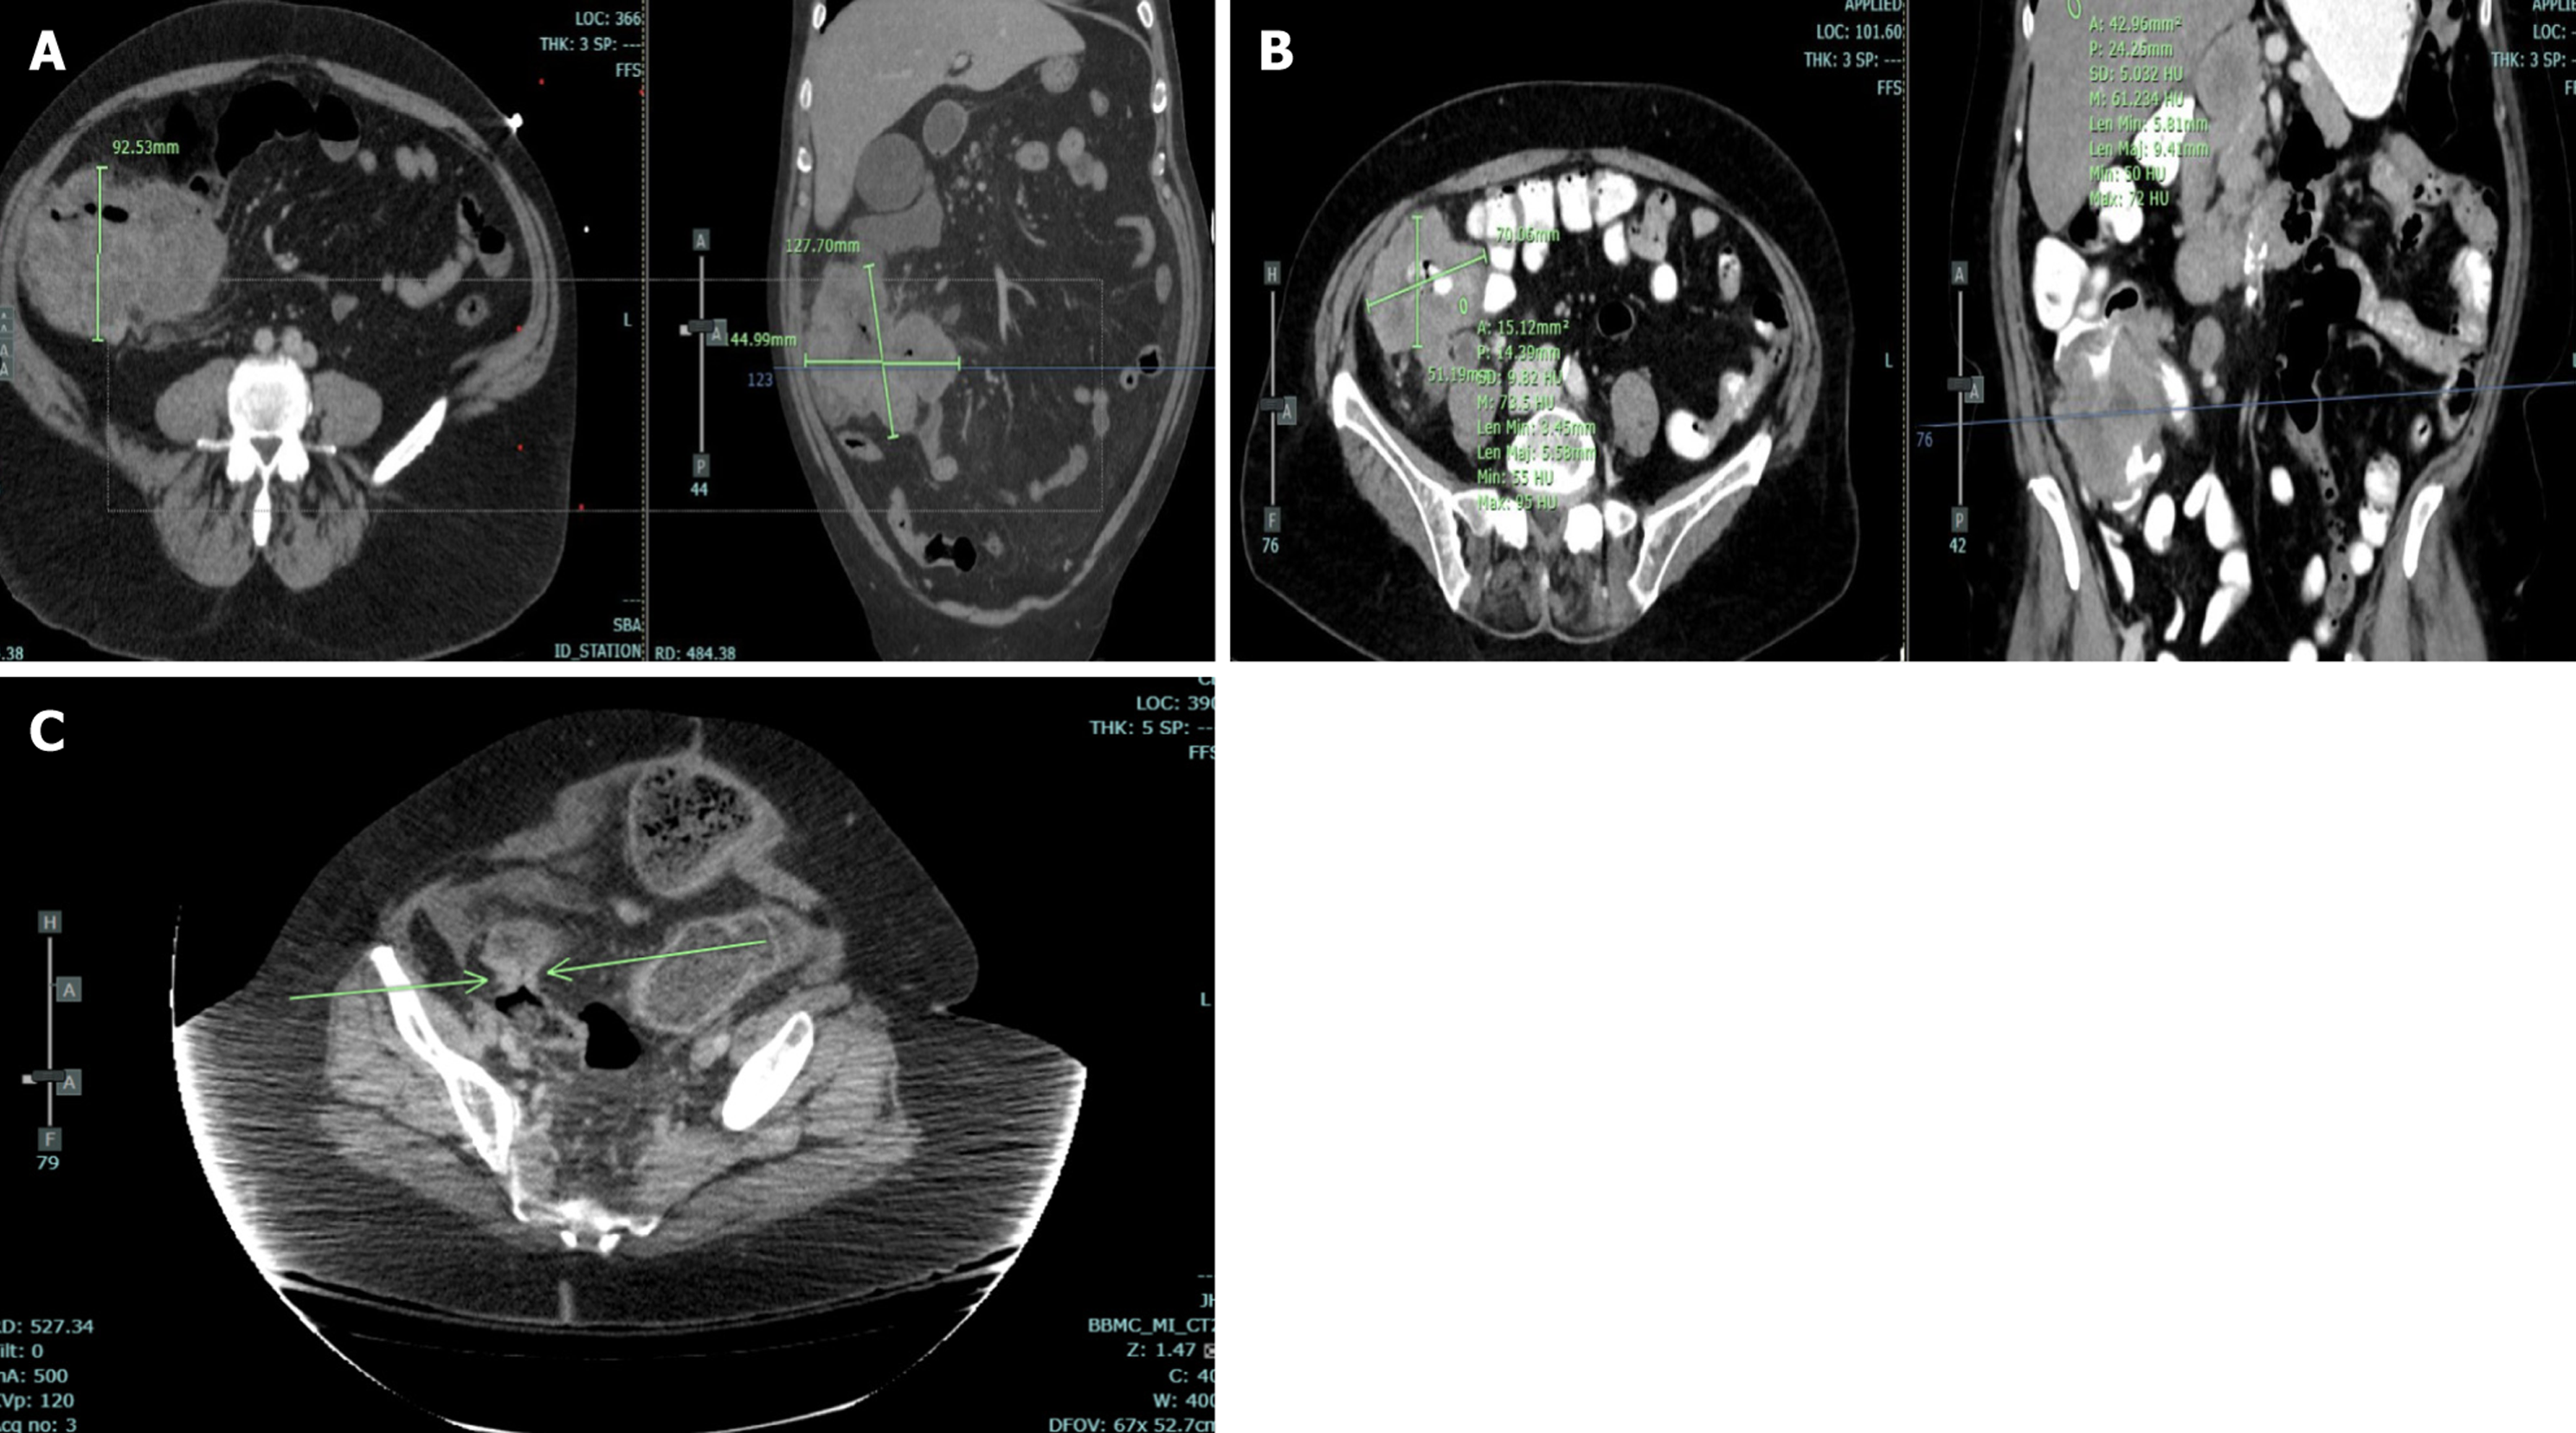

Imaging data are obtained according to the following description. Size of the primary tumor is obtained in the axial plane on the image with the largest cross-section area. The size is then measured along the longest axis with the short-axis measurement obtained perpendicular to the long axis to obtain the largest cross-section area of the tumor. Lymph nodes are considered abnormal if the short axis is ≥ 1 cm or if the nodes are rounded in appearance. Metastasis is determined by pathology report or clinical notes. Tumor heterogeneity/content classification was determined if the primary mass has at least 30% of the area being different in density than the dominant, enhancing area. The type of growth pattern is classified as either along the wall or mass-like. Growth along the wall is when the mass extends mostly along the wall of the colon while mass-like growth tends to be rounded or polypoid in morphology. Tumor margin is classified as either well-defined or ill-defined. Well-defined tumors have sharply marginated borders whereas ill-defined tumors have borders that could not clearly be identified. Mesenteric infiltration is defined as whether or not the images show pericolonic stranding. This definition may be confounded by the edema that is present rather than true tumor infiltration. Unfortunately, with CT, this difference could not be clearly differentiated. Primary tumor enhancement is determined relative to the normal liver density. It is considered hypoattenuating if the density is less than normal liver while hyperattenuating is density greater than normal liver. Isoattenuating is when the mass density is within ± 10% of the liver attenuation. The density is measured in the enhancing regions of the primary mass by using a rounded region of interest measurement tool with at least 0.5 cm diameter. An example of the features described above are shown in Figure 3.